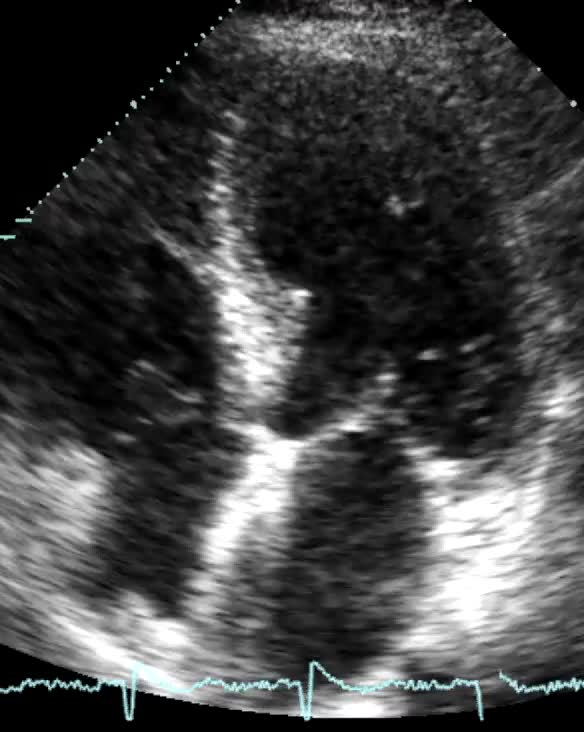

Titolo:

Stenosi mitralica

Autore:

Chiara Bencini